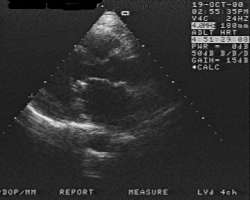

Характерным электрокардиографическим признаком являются отклонение электрической оси сердца вправо, признаки гипертрофии правого желудочка и левого предсердия, а также мерцательной аритмии в более поздние стадии заболевания. Фонокардиографические признаки, как правило, соответствуют да иным аускультации. Весьма характерны эхокардиографические данные, позволяющие с большой точностью измерить митральное отверстие, составить представление о характере анатомических изменений клапана (рис. 2, а, б), распознать наличие тромбоза левого предсердия и оценить функцию сердца.

![]() | Рис. 2. А Эхокардиографическое исследование больного с митральным стенозом в В-режиме по продольной оси. Митральное отверстие сужено, с отложениями кальцинатов по свободному краю. |

![]() | Рис. 2. Б Эхокардиографическое иследование у того же больного по короткой оси. Визуализируется митральный клапан. Отверстие резко уменьшено, в виде «рыбьего рта». |